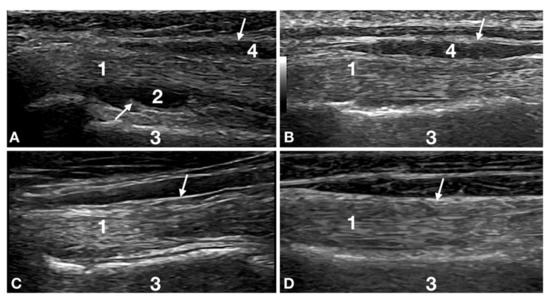

2.3. Ultrasound Evaluation